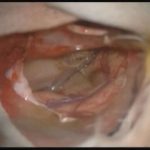

術中写真

摘出 中

摘出 後